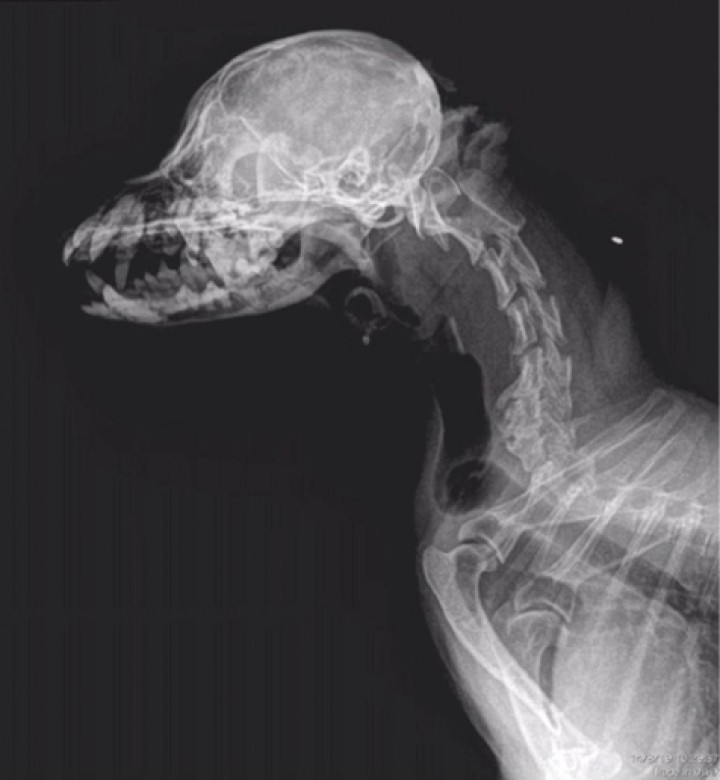

Acude de urgencias a consulta un Yorkshire terrier macho castrado de 13 años de edad y 2 kilos de peso. Tras un episodio de estrés en su clínica de referencia, el animal comenzó a ladrar y “llorar” observándose una grave dilatación en la zona ventral del cuello, la cual aparecía con cada gemido. En la exploración realizada en el Hospital Clínico Veterinario de la Universidad de Extremadura, todas las constantes se encuentran dentro de la normalidad y no se observan anomalías en el cuello ni en la entrada del tórax a la palpación y presión traqueal, incluso tras provocarle la tos. No hay historial de traumatismos ni problemas respiratorios previos. No se observan anomalías relevantes en la hematología y bioquímica completa. Nos remiten una radiografía de cráneo y cuello latero-lateral derecha (Fig. 1) y se realiza a su llegada al HCV de la UEx una radiografía torácica latero-lateral derecha de tórax (Fig. 2).

<p>Proyección latero-lateral derecha de la región cervical incluida la cabeza. Imagen cedida por la Clínica Veterinaria Azureus.</p>

Proyección latero-lateral derecha de la región cervical incluida la cabeza. Imagen cedida por la Clínica Veterinaria Azureus.